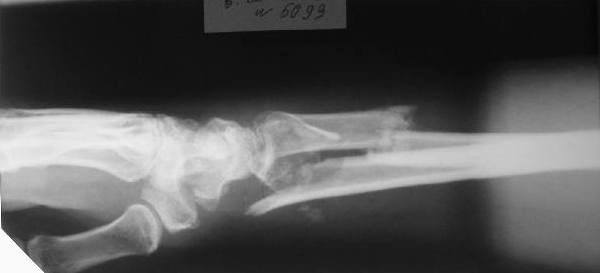

перелом Н/3 предплечья

Больному 27 лет. Травма 2 месяца назад, проводилась закрытая репозиция. Контрольные снимки 3 недели назад (смотреть вложение).

Планируем провести открытую репозицию фиксацию пластинами.

Обдумываем, как провести репозицию? Предварительно провести дистракцию аппаратом внешней фиксации за нескольких дней до открытой репозиции или во время открытой репозиции?

Первоначальное впечатление: если край проксимального отломка лучевой кости не давит на срединный нерв и не нарушает скольжение сгибателей, то достаточно быстро пациент сможет вернуться к труду при продолжении консервативного лечения. Укорочение на 15 мм для неопорного (да и для опорного тоже) сегмента некритично. Имеющиеся осевые смещения вполне компенсируются запасом диапазона фукции суставов. Если край проксимального отломка мешает -- можно резецировать его, не разрушая сфорировавшегося к сегодняшнему дню сращения.